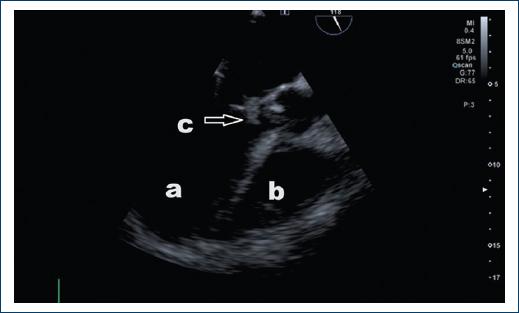

Blood cultures were performed with growth of Enterococcus faecalis, in addition to transthoracic echocardiogram showing large vegetation (area of 3.2 cm) with pedicle adhered to the non-coronary leaflet (Fig. 1), producing severe aortic regurgitation, moderate mitral regurgitation, severe tricuspid regurgitation (Fig. 2), so management with meropenem, vancomycin and gentamicin was indicated for 14 days. A transesophageal echocardiogram was performed, and a) vegetation in the anterior mitral leaflet of 14 mm in size with perforation of the leaflet with aortomitral continuity (Figs. 2A and B).

Figure 1 Transthoracic echocardiogram image (parasternal long-axis view). a: left ventricle, b: left atrium, c: vegetation in a large aortic valve of 3.2 cm (arrow).